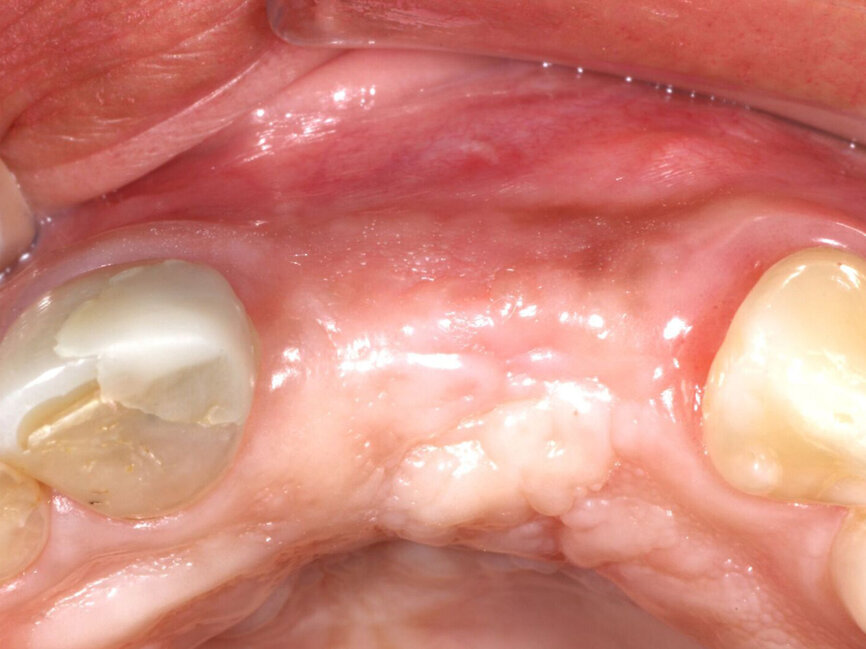

A 52-year-old male patient presented missing the left central and lateral maxillary incisors with a desire to have implants to replace the missing teeth and a fixed prosthetic approach. The patient indicated that the teeth had been extracted eight years before, and clinical examination noted a deficient facial aspect of the ridge at the extraction sites and healthy soft tissue (Fig. 1). A cone-beam CT (CBCT) was taken and evaluated. Cross-sectional views of the edentulous space confirmed inadequate width of the ridge in the facial-palatal dimension to house implants at the adjacent sites (Fig. 2). The patient was informed of the clinical findings and a discussion on augmenting the site with an osseous graft would be necessary for implant placement. As insufficient bone would not permit simultaneous implant placement at the time of grafting, the patient was informed that a healing period of four to six months would be needed between graft placement before implants could be placed. This would then be followed by a four- to six-month period to allow the implants to osseointegrate before any restoration could be placed on the implants. The patient agreed to treatment and was appointed.

A #15 scalpel was utilized to create a vertical releasing incision between the right canine and lateral incisors and also between the left first and second premolars. These were connected by a facial sulcular incision medial to the vertical releasing incisions and a midcrestal incision at the edentulous area. A full thickness flap was elevated extending past the mucogingival junction to exposure the deficient area as well as bone covering the roots of the adjacent teeth (Fig. 3). A thin ridge with a notable concavity at the edentulous area was confirmed correlating with what was accessed on the CBCT exam. A three sided 1.2 mm bur from MedEquip Dental Supplies in a surgical handpiece was utilized to create multiple decortication points through the cortical bone to the underlying cancellous bone (Fig. 4). This is performed to allow endosteal osteoblasts from the cancellous bone to interact with the graft, grow bone around and within the particulate graft particle, and to accelerate vascularization of the graft and incorporation to the osseous bed.